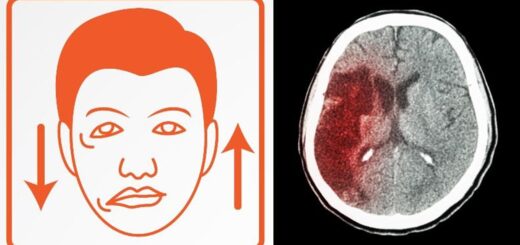

Podle posledních statistik jsou mozkové mrtvice hlavním faktorem invalidity u dospělých lidí a čtvrtou nejčastější příčinou úmrtí. Mozková mrtvice je podobný stav jako srdeční infarkt, akorát s...